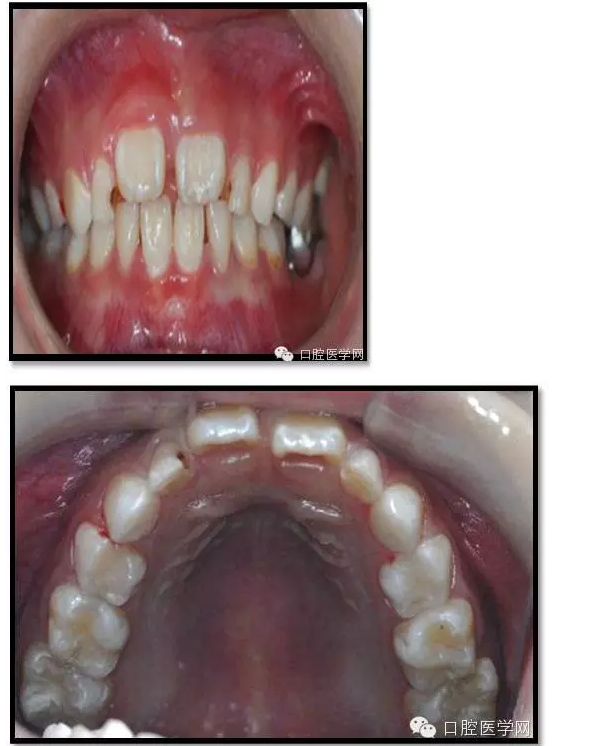

治療結(jié)束后3個月復查

復查:無不適

檢查:口腔衛(wèi)生一般,牙面軟垢菌斑中量。 85O、84DO充填完好,邊緣密合,叩(-),不松,齦無紅腫。

75帶環(huán)絲圈式間隙保持器完好,無松動,無咬合不適。

余牙充填體完好密合,未查及繼發(fā)齲和新發(fā)齲壞。

治療結(jié)束后7個月復查

85O、84DO充填完好,邊緣密合,叩(-),不松,齦無紅腫。X線:84、85根分歧透射影,44、45骨硬板連續(xù),恒牙胚上方骨板厚約2-3mm。75帶環(huán)絲圈式間隙保持器完好,無松動,無咬合不適。64MO中齲。 64MO中齲去腐凈,自酸蝕,SEBOND,樹脂充填。 口腔衛(wèi)生宣教,囑3個月后復診。